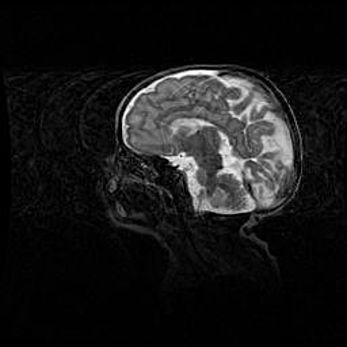

Открытая гидроцефалия.

Возраст: 9 месяцев 12 дней

Вес: 6800 г

Пол: мужской

Окружность головы: 41,5 см

Срок гестации: 28 недель

Гидроцефалия головного мозга у новорожденных имеет характерный признак: опережающий рост окружности головы приводит к визуально хорошо определяемой гидроцефальной форме сильно увеличенного в объёме черепа. Детские неврологи определяют следующие симптомы гидроцефалии у грудничков: выбухающий напряжённый родничок, частое запрокидывание головы, смещение глазных яблок к низу.